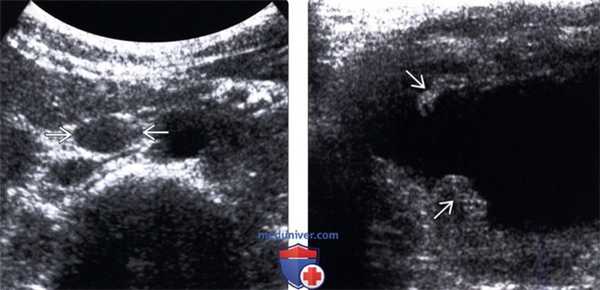

(Левый) На поперечном трансабдоминальном ультразвуковом срезе визуализируется увеличенный парааортальный лимфатический узел у пациента с туберкулезом (ТБС) почки. Сочетанная лимфаденопатия встречается часто и может быть реактивной, либо инфекционной.

(Правый) На поперечном трансабдоминальном ультразвуковом срезе визуализируется ТБС мочевого пузыря (неравномерно утолщенные стенки пузыря) Картина может быть неотличима от любых других форм бактериального цистита.